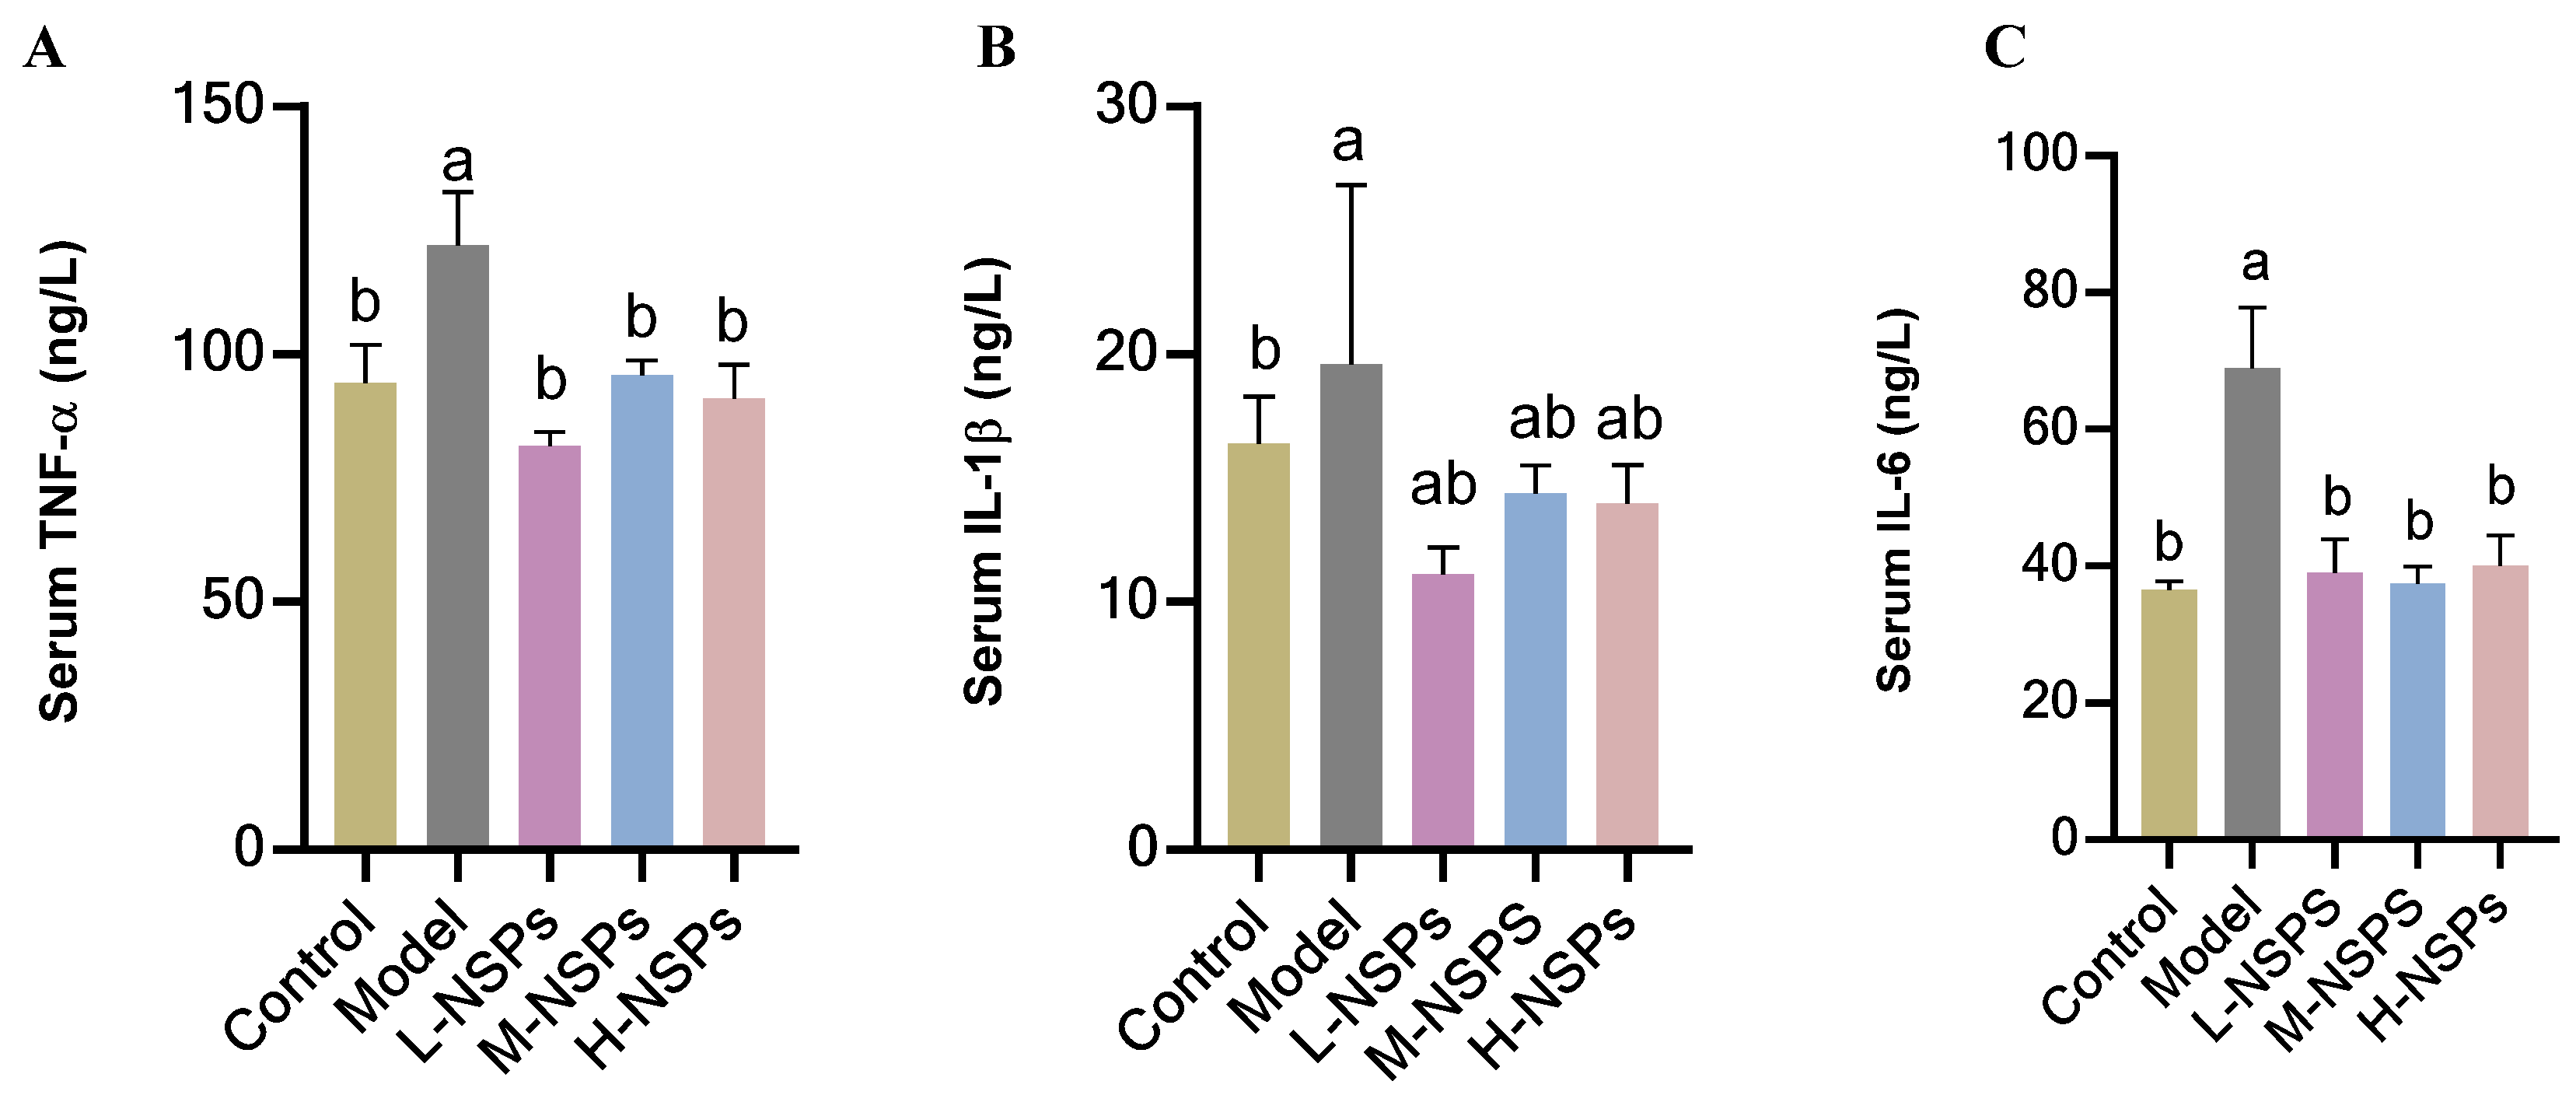

3.12. The Effect of NSPs on the Inflammatory Response in Diabetic Mice